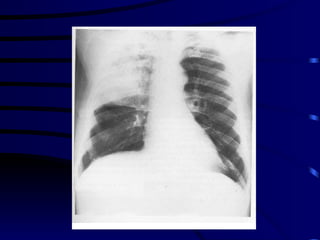

Definition Syndrome caused by acute infection caused by a wide variety of microorganisms, characterized  by clinical and/or radiological signs of consolidation of a part or parts of one or both lungs .

Clinical Definition Symptoms of acute LRT infection  a) Cough, sputum,chest pain b) Fever,sweating,shiver, aches and pains New focal chest signs on examination  OR New  radiographic pulmonary infiltrates

SEVERE CAP There is no universally accepted definition of severe CAP: 1. Respiratory frequency >30 breaths min at admission 2. Severe respiratory failure defined by a Pao2/Flo2 ratio <250  3. Requirement for mechanical ventilation 4. Chest radiograph showing    a) bilateral involvement    b) involvement of multiple lobes   c) an    in the size of the opacity by   50 % within 48 h of  admission  5. Shock ( SBP < 90 mmHg or DBP < 60 mmHg)  6. Requirement for vasopressors for more than 4 h 7. Urine output < 20 ml/h or acute renal failure requiring dialysis

SOME FACTS ABOUT CAP The  etiologic agent  causing CAP cannot be accurately predicted from clinical or radiological features The term ‘ atypical pneumonia ’ should be abandoned Elderly patients  with CAP more frequently present with non specific symptoms and are less likely to have fever Radiological resolution  lags behind clinical improvement  Radiological resolution  is slow in the elderly and cases of multilobar involvement.